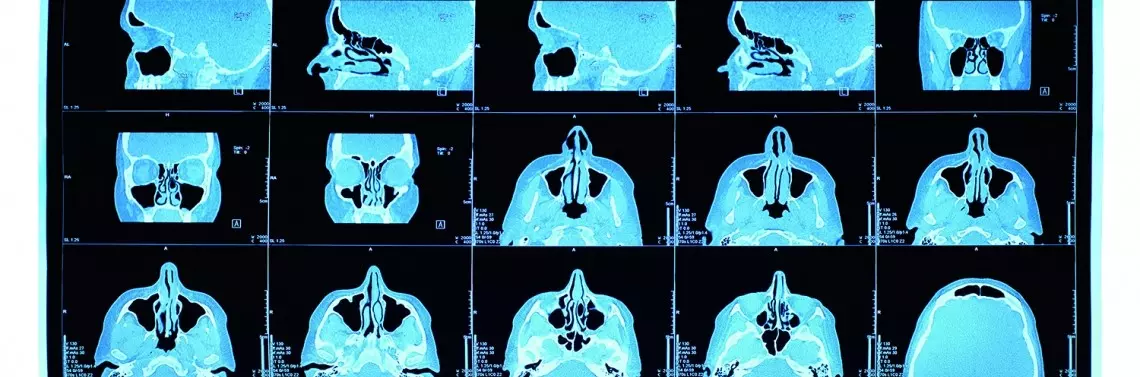

Największe objętościowo zatoki szczękowe poprzez górną ścianę graniczą z dnem oczodołu, natomiast ściana przednio-dolna zatok szczękowych sąsiaduje z górnymi zębami (zdj. 1).

Zdj. 1

Poprzez przez swoją lokalizację zatoki szczękowe są podatne na powikłania spowodowane źle dobranym leczeniem zębów, w tym leczeniem implantologicznym. Jednocześnie przewlekłe zapalenie zatok może prowadzić do zmian okołokorzeniowych zębów5.

Przed przystąpieniem do zabiegu podniesienia dna zatok należy najpierw przeprowadzić diagnostykę laryngologiczną, a w przypadku stwierdzenia zmian patologicznych w obrębie zatok zastosować odpowiednie leczenie. Niezbędne procedury przed przystąpieniem do zabiegu Sinus lift to szczegółowy wywiad − badanie podmiotowe, badanie kliniczne przedmiotowe oraz badania radiologiczne. Badanie tomografii komputerowej jest pomocne w określeniu jakości i liczby kości wyrostka zębodołowego. Dzięki temu umożliwia diagnozę ewentualnej patologii zatoki szczękowej12. Tomografia komputerowa to złoty standard w diagnostyce zatok ze względu na jej zdolność do zapewniania wielu przekrojów przez zatokę w różnych płaszczyznach. Chociaż głównym wskazaniem do tomografii zatoki szczękowej jest podniesienie dna zatoki i ocena radiologiczna szczęki przed umieszczeniem implantu dentystycznego, ta metoda obrazowania jest coraz częściej stosowana również w celach endodontycznych i periodontycznych13.